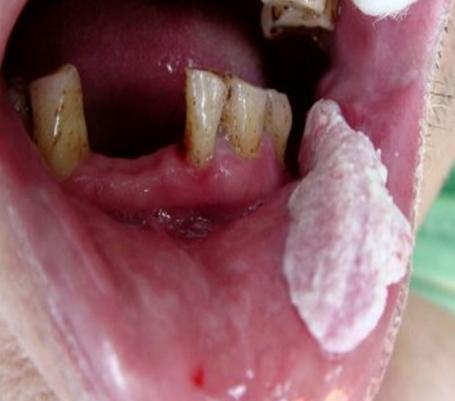

陈忠实为什么会得舌癌,陈忠实的舌癌做了什么治疗癌前病变——疣状增生↑

癌前病变是指具有潜在恶性转变可能的病变。超过两周不痊愈的慢性口腔溃疡,要警惕了,这可能是口腔癌的癌前病变。口腔癌的癌前病变还包括黏膜红斑、黏膜白斑、黏膜下纤维化、疣状增生、慢性溃疡等。癌前病变如果长期不治疗或者是刺激源一直存在,那么这样的病变转变为口腔癌的可能性就很高。例如,口腔内有尖锐蛀牙,或者残余的牙根对口腔形成慢性刺激,就有可能加大罹患口腔癌的潜在风险。